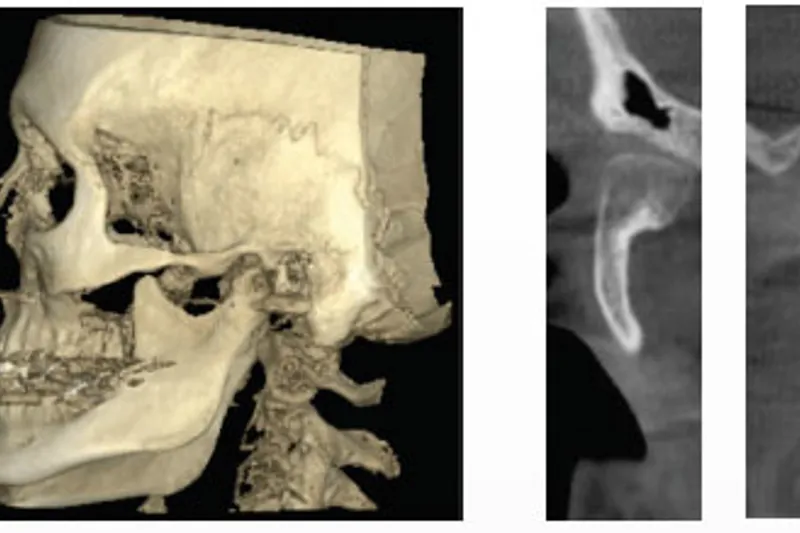

– Hemimandibulær hyperplasi (HH) er en udviklingsbetinget, tredimensionel forstørrelse af den ene halvdel af mandiblen, hvilket resulterer i asymmetri med okklusale, funktionelle og æstetiske problemer til følge. HH viser sig klinisk i puberteten. Behandlingen afhænger af vækstaktiviteten. Øget vækstaktivitet i et eller begge kæbeled kan diagnosticeres med en knoglescintigrafi og ved behandling og observation med en bidskinne. Ofte er det nødvendigt at korrigere både maksillen og mandiblen i behandlingen af den dento- faciale deformitet, fordi den maksillære vækst kompenserer for vækstafvigelser i mandiblen. Formålet med denne artikel er at belyse ætiologi, forekomst og behandling af hemimandibulær hyperplasi. Som illustration gennemgås en gruppe patienter behandlet på Kæbekirurgisk Afdeling, Aarhus Universitetshospital.

– Hemimandibulær hyperplasi bør diagnosticeres og behandles så tidligt som muligt med henblik på optimal vurdering af unormal vækstaktivitet og vækstmønster. Kompensatorisk vækst og dento-alveolære forandringer minimeres herved, og delvis kondylektomi bør overvejes i tilfælde med aktiv vækst. Det er ofte nødvendigt med en kirurgisk korrektion på begge kæber for at korrigere asymmetrien på mandiblen og maksillen. Det er vanskeligt at forudsige stabiliteten af den ortokirurgiske behandling, da hyperaktiv vækst kan vende tilbage efter såvel kondylektomien som det korrigerende indgreb. Ætiologien er ukendt, selvom genetiske faktorer, tidligere traume og infektion bl.a. diskuteres som mulige faktorer.